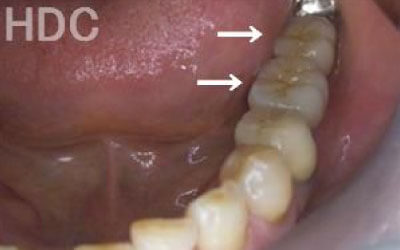

しばらくすると抜けたままでも慣れてきますが、大きな問題が発生します。

2 歯が傾いてくる、落ちてくる

歯はお互いに支え合ってバランスを取っています。ですので、歯が抜けるとその支えがなくなり、抜けた部分の隣の歯が倒れたり、上の歯が下に下がってくることがあります。